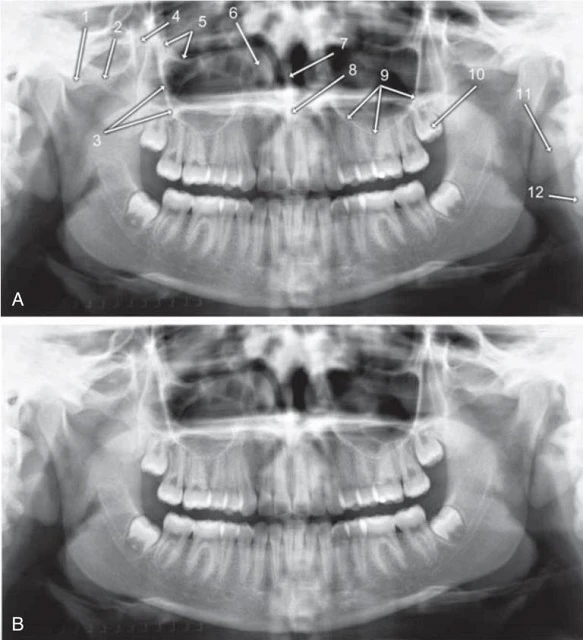

Hình 17. Cấu trúc giải phẫu xương hàm dưới trên hình ảnh phim x-quang toàn cảnh. Hình ảnh A và B là hai hình trùng lặp của cùng một bệnh nhân. 1, Lồi cầu xương hàm dưới. 2, Cổ lồi cầu xương hàm dưới. 3, Mõm vẹt xương hàm dưới. 4, Hình ảnh ma, mặt sau của bờ dưới hàm dưới bên trái. 5, Ống thần kinh xương ổ răng dưới. 6, Bờ dưới xương hàm dưới. 7, Hình chồng lên của bóng đốt sống cổ. 8, Lỗ cằm. 9, Hõm dưới hàm (chỗ lõm tại vị trí tuyến nước bọt lưỡi). 10, Góc hàm. 11, Gờ chéo ngoài. 12. Hõm xích ma.

Hình 18. Những cấu trúc giải phẫu đốt sống, cổ và mô mềm trên phim x-quang toàn cảnh. Hình ảnh A (có ghi chú) và B (không ghi chú) trùng nhau của cùng một bệnh nhân. 1, Schmorl’s Node (biến thể giải phẫu bình thường của thân đốt sống). 2, Đốt sống cổ. 3, Thuỳ tai. 4, Khẩu cái mềm và lưỡi gà. 5, Khẩu cái cứng (đường phía dưới là chỗ nối giữa khẩu cái cứng và thành bên của xoang mũi bên phía receptor). 6, Vành ổ mắt. 7, Sàn vòm họng (mặt trên khẩu cái mềm). 8, Mặt sau của lưỡi. 9, Thành sau họng. 10, Xương móng.